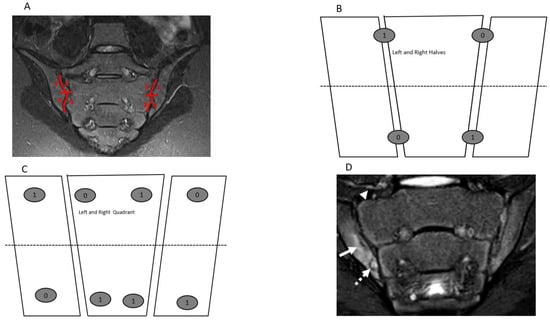

| Features | Definitions | Scores |

|---|---|---|

| Inflammation MRI Components | Score range/slide | |

| BME | An ill-defined area of high bone marrow signal intensity † within the subchondral bone in the ilium or sacrum on fluid-sensitive images | Score 4 quadrant/SIJ 0/1, range 0–8 |

| BME Intensity | Hyperintensity of the marrow edema using the presacral veins as reference | Score each SIJ 0/1, 0–2 |

| BME Depth | Continues to increase the signal of depth ≥ 5 mm/ ≥ 1 cm from the articular surface | Score each SIJ 0/1, 0–2 |

| Capsulitis | High signal on fluid-sensitive and/or post-contrast enhancement involving the SIJ capsule | Score halves / SIJ 0/1, 0–4 |

| JSI | Increased signal on fluid-sensitive or contrast-enhanced T1-weighted images within the joint space of the cartilaginous portion of the SIJ | Score halves/ SIJ 0/1, 0–4 |

| Enthesitis | High signal in bone marrow and/or soft tissue on a fluid-sensitive sequences or a contrast-enhanced T1-weighted sequence at sites where ligaments and tendons attach to a bone | Score each case 0/1, 0–1 |

| Structural MRI Components | ||

| Sclerosis | A substantially wider than normal area of low subarticular bone signal on T1-weighted and fluid-sensitive images (of ≥5 mm in adolescents) | Score 4 quadrants/SIJ 0/1, 0–8 |

| Erosion | Bony defect (or irregularity with associated bone marrow edema, sclerosis, or fatty lesion) at the osteochondral interface involving both contour and signal on both T1-weighted and fluid-sensitive images | Score 4 quadrants/SIJ 0/1, 0–8 |

| Fat Lesion | Increased homogenous signal intensity on T1-weighted non-FS image in subchondral bone with a distinct border | Score 4 quadrants /SIJ 0/1, 0–8 |

| Backfill | A bright signal on a T1-weighted sequence in a typical location for an erosion, with signal intensity greater than normal bone marrow, and meeting the following requirements. 1. It is associated with complete loss of the dark appearance of the subchondral cortex at its expected location. 2. It is clearly demarcated from adjacent bone marrow by an irregular band dark signal reflecting sclerosis at the border of the original erosion | Score halves/SIJ 0/1, 0–4 |

| Ankylosis | Presence of signal equivalent to regional bone marrow continuously bridging a portion of the joint space between the iliac and sacral bones | Score halves/0/1, 0–4 |